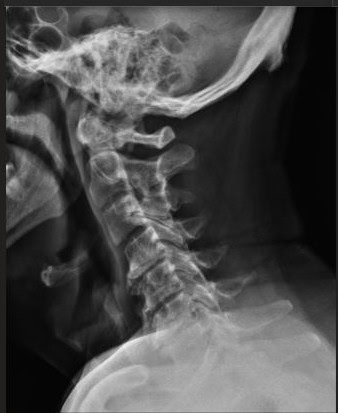

Pre Scan